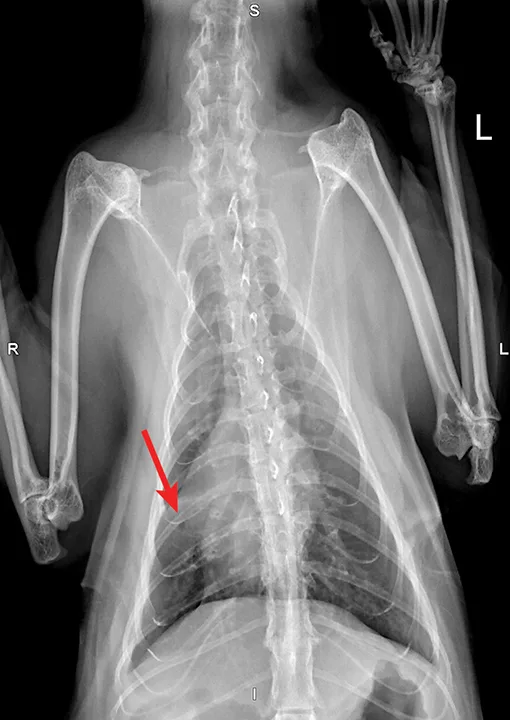

FIGURE 5A

Radiograph of aelurostrongylus abstrusus infection (lungworm). Note the diffuse bronchial pattern (orange arrows), patchy poorly defined soft-tissue nodules (red arrows), and right middle lung lobe alveolar disease (yellow arrow). This pattern could be confused with feline asthma in this case; however, the right middle lung does not appear atelectatic but instead infiltrated. Fine-needle aspiration of the right middle lung lobe confirmed larvae.